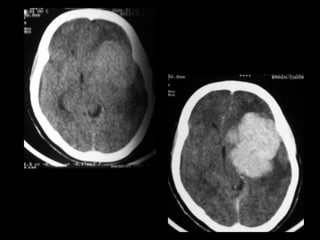

CT of intracranial meningiomas

• Plain CT- isodense to slightly hyperdense relative to

brain parenchyma

• Density homogenous & sharply marginated

• Calcification- a) tiny punctate (psammomatous)

is common

b) dense calcification of entire

lesion

c) nodular calcification, less

common

Contrast CT

• Homogenous, intense enhancement

• Result of passage of iodinated contrast material

into the interstitial space of neoplasm, rather than

hypervascularity

• Being extra-axial has no blood brain barrier

• Margins sharp & broadly based against a bony

structure or a free dural edge

Coronal scanning

• Relationship to bony

structures, as well as

dural structures

demonstrated

• Displacement of vessels

• Contiguous bony structures altered, either due to

direct infiltration or because of reactive changes to

hypervascularity of the neoplasm

• Commonest finding is hyperostoses

• New bone less homogenous & has irregular

margins

• Bony erosion by pressure from an adjacent tumor

CT signs S/O aggressive course

• Heterogeneous contrast enhancement

• Indistinct or irregular margins

• Minimal or no calcification

• Marked surrounding edema

• Mushroom-like projections